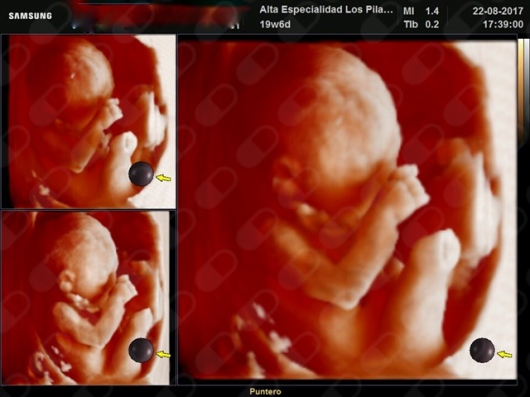

Fotos y videos